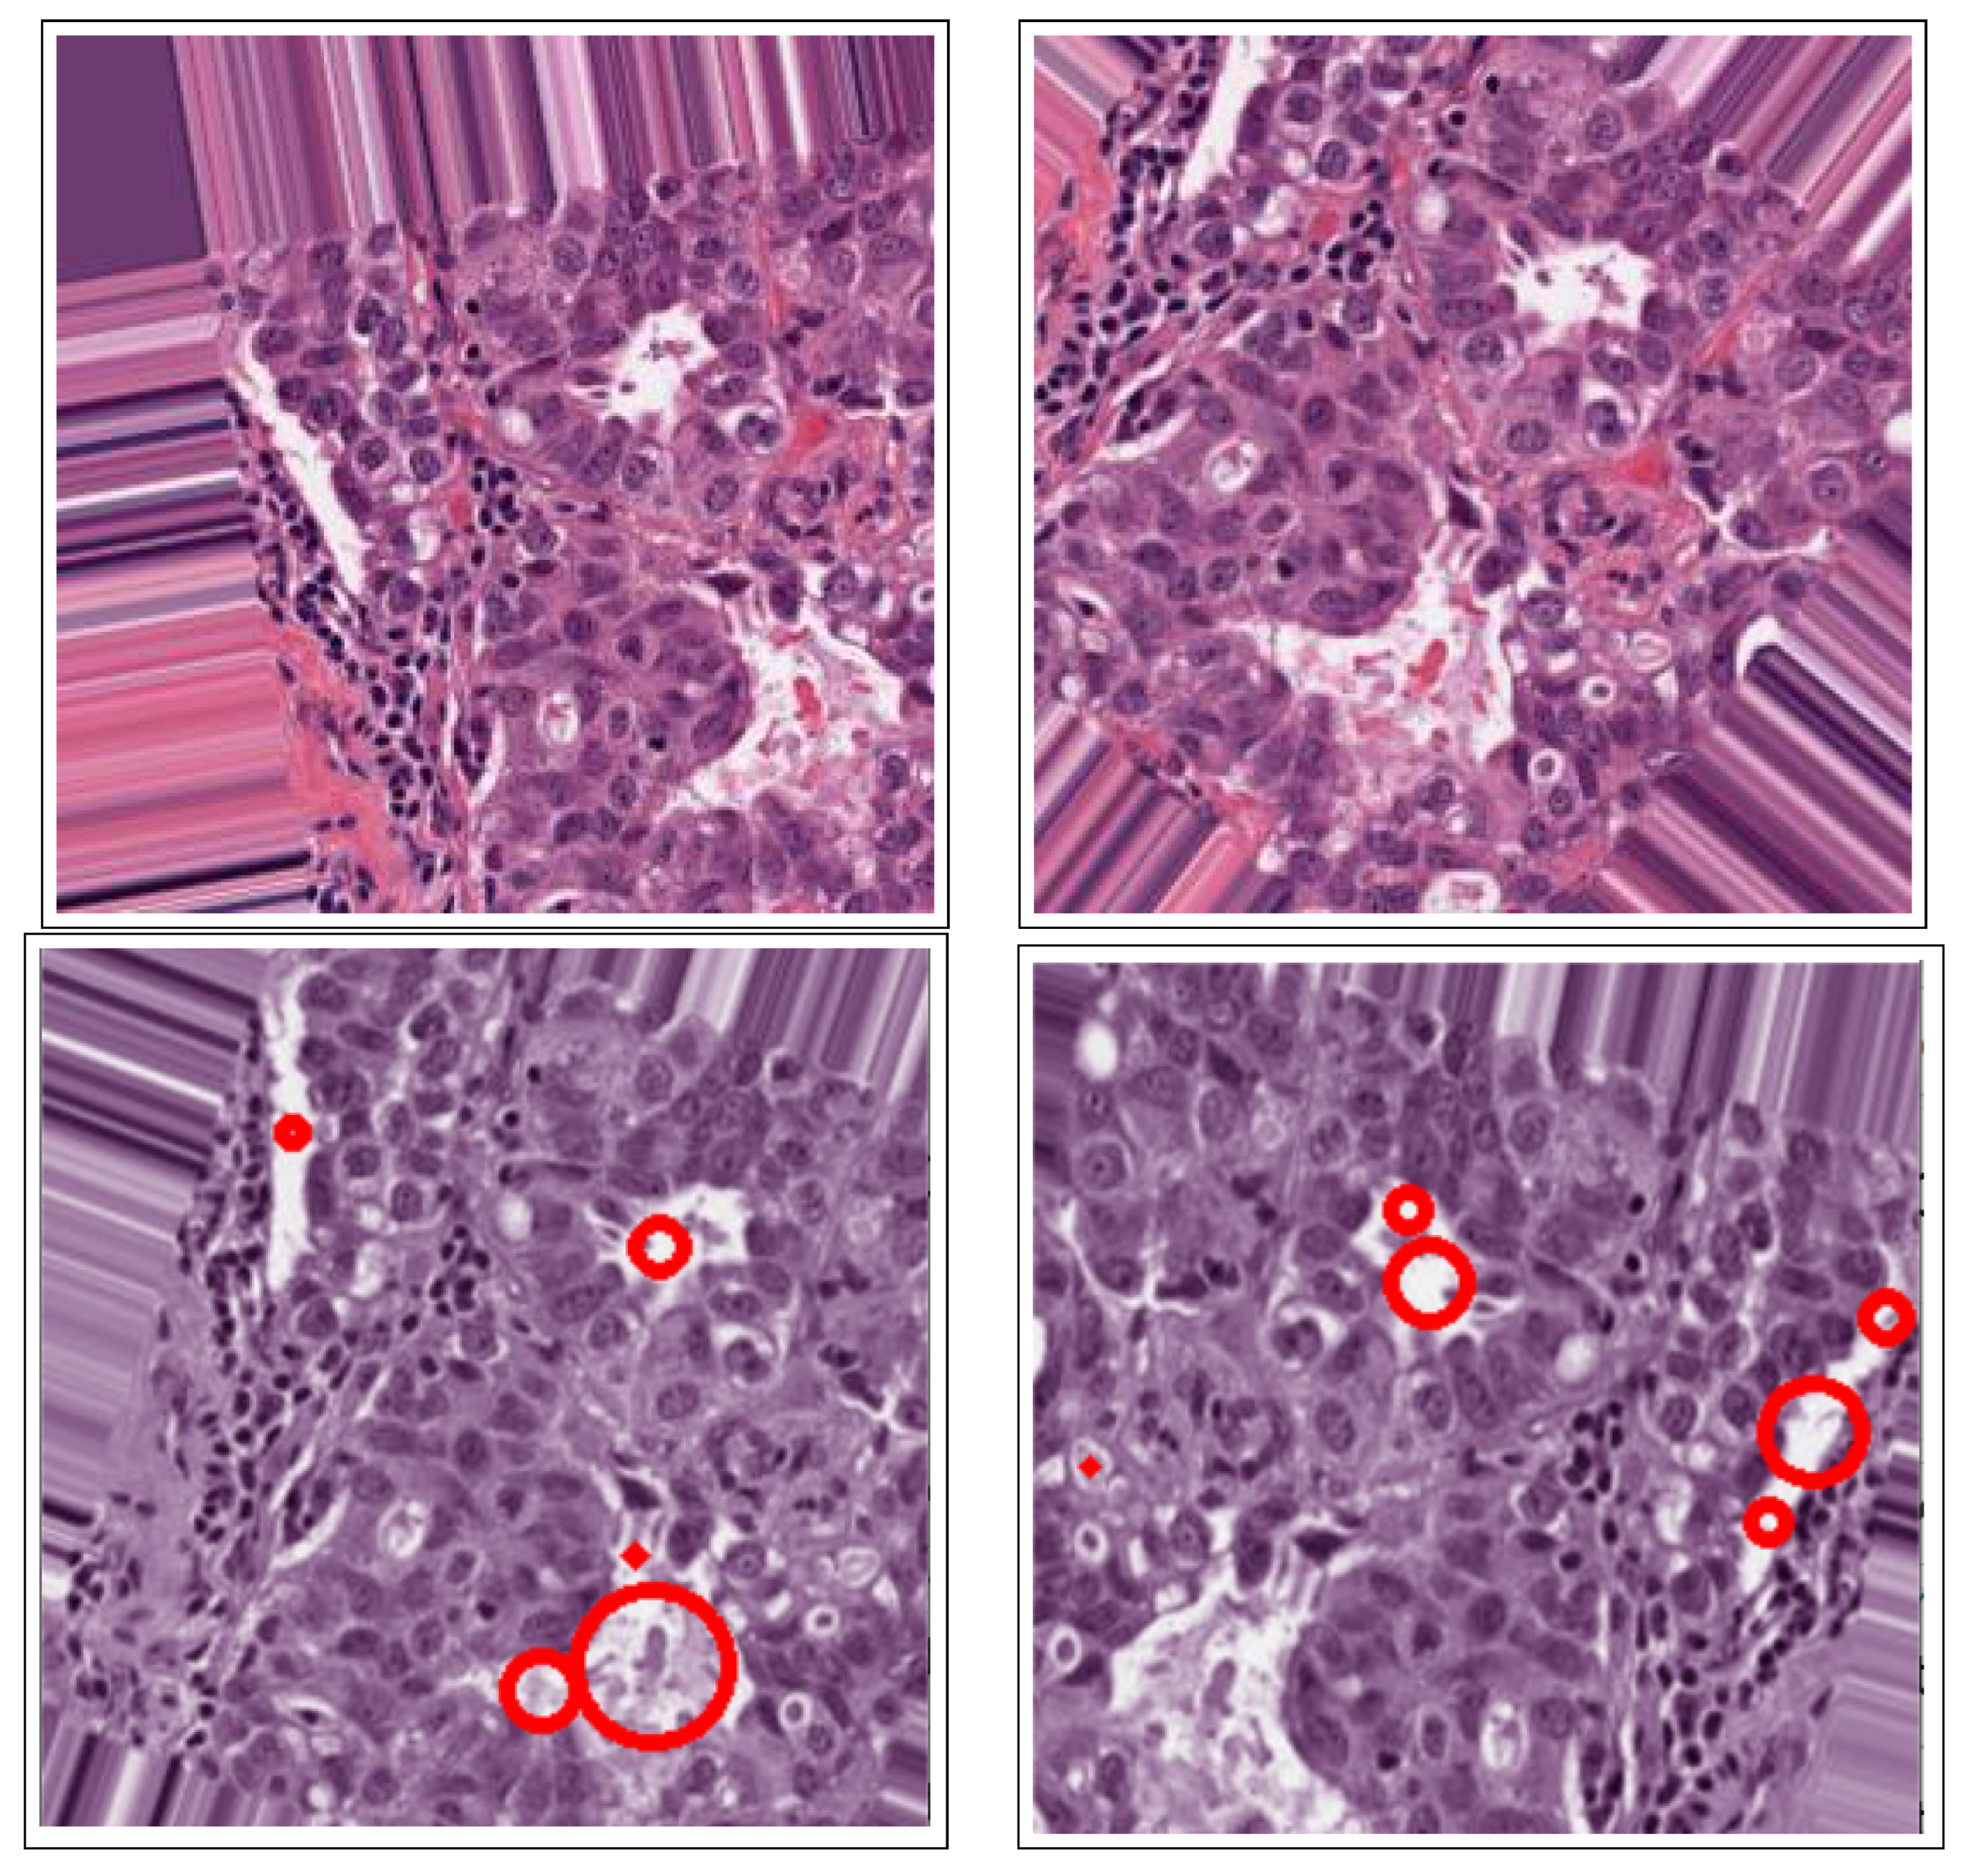

- The use of the connected component analysis method to group components with similar characteristics into binary masks that assist in separating overlapping and non-overlapping objects, thus avoiding over-segmentation.

- The binary masks from the connected component analysis method further aid in addressing the inaccurate segmentation of the image boundaries of intersecting objects, which is common with the active contours method. The proposed method clearly distinguishes the different ROIs from each other, clearly isolating and segmenting the cancerous lesions as visually documented in Section 3 and Section 4.